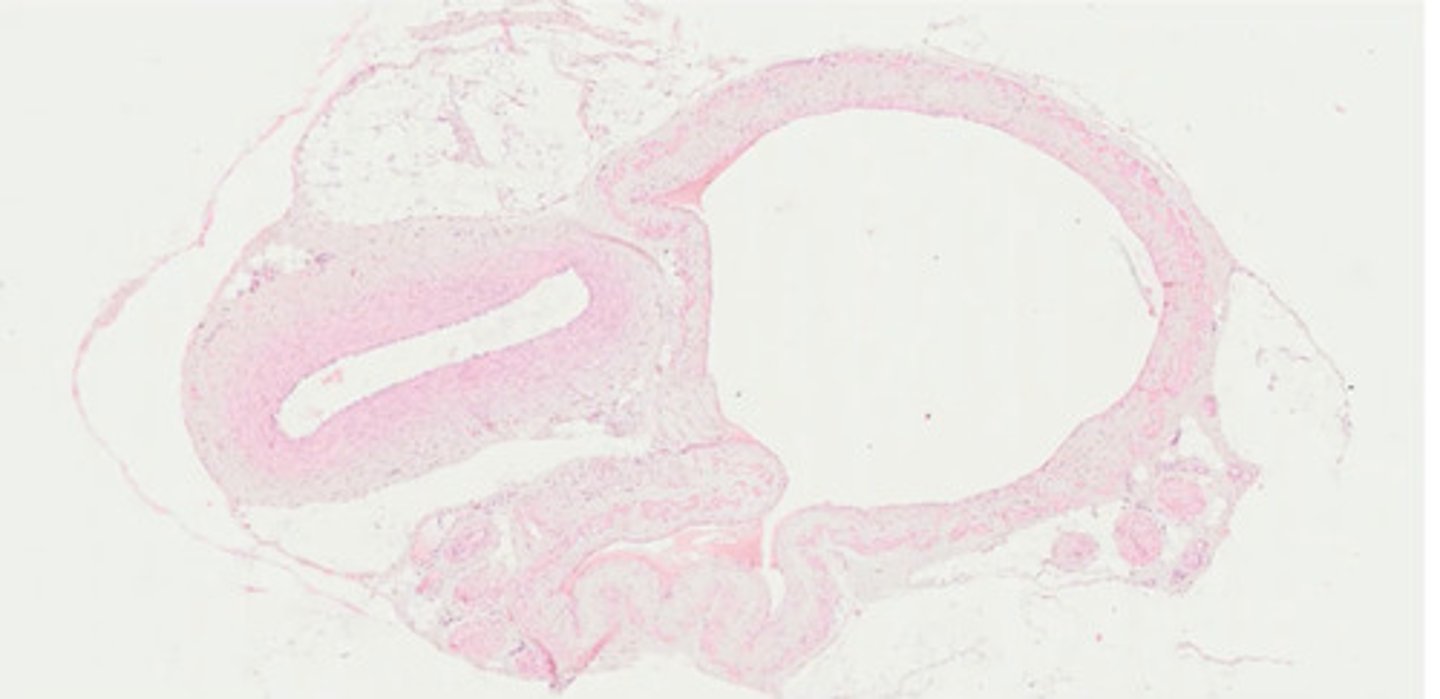

Oko - przekrój strzałkowy (H+E)